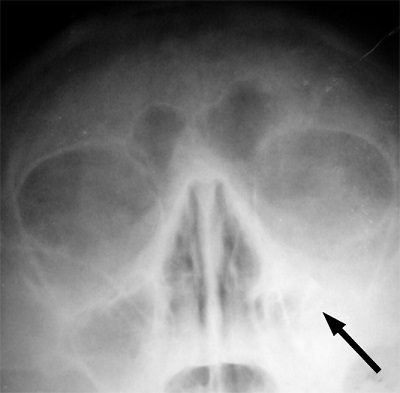

特に副鼻腔、口蓋扁桃、上咽頭、顎骨(神経を抜いた歯の根っこ)、胆嚢、虫垂などがチェックポイントです。

↑副鼻腔炎の画像。画像の右が白く見えるところ。(画像はウィキペディアより)

特に顎骨病巣感染がやっかいでしょう。顎骨病巣感染では、顎骨が腐敗したり膿が溜まっていて、そこから常に全身に毒素がばら撒かれる状態となります。